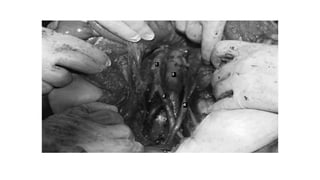

Procedure of surgical staging

The patient is placed in the supine position or the dorsal modified lithotomy

position with the hips slightly abducted, the thighs parallel to the floor, and the

knees flexed in obstetric stirrups.

The incision should extend from the symphysis pubis to well above the umbilicus

and, in many cases, up to the xiphoid.

If malignancy is unexpectedly discovered in lower transverse incision; rectus

muscles can be divided or detached from pubis ; or incision can be converted in to j

shape.

Any ovarian tumor should be removed intact; if possible frozen section should be

obtained.